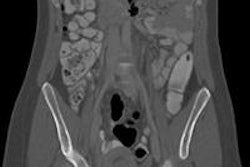

Such methods are vital for estimating radiogenic risk during any justification and optimization process for CT examinations in pregnant patients. For example, if a pregnant patient with abdominal pain was admitted to a hospital to rule out appendicitis, but the appendix was not visualized adequately with ultrasound, physicians might request abdominal CT with and without contrast. "Radiologists need to weigh up the risk of irradiating the conceptus against that of not making the necessary diagnosis," he said.